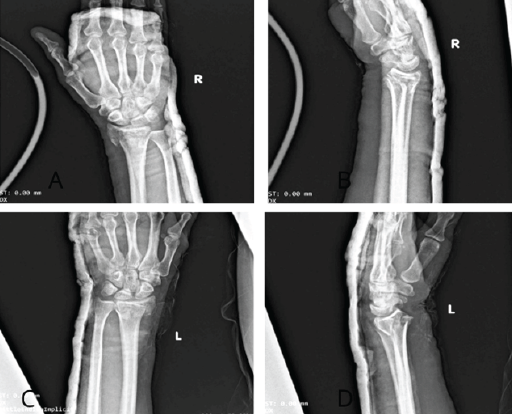

A 42-year-old right-handed male construction worker fell from a scaffold approximately 10 feet high. He landed with both arms outstretched and elbows extended. Upon presentation, the patient had gross deformity, pain, and swelling at both wrists and elbows. Upon inspection, deformities were seen on both wrists and elbows bilaterally. On examination, tenderness was found with a limited range of motion. Neurovascularity was intact in both upper limbs. X-rays revealed bilateral posterior elbow dislocation without associated fracture (Fig. 1a, b, c, d) and bilateral comminuted intra-articular distal radius fractures (AO 23-C2). (Fig. 2a, b, c, d). In the emergency setting, both elbow dislocations were promptly managed with closed reduction under sedation, and concentric reduction was confirmed on post-reduction radiographs (Fig. 3a, b, c, d). Both wrists were also reduced, and stabilization was done with slab application (Fig. 4a, b, c, d). Following initial stabilization and resolution of soft tissue swelling, the patient underwent staged open reduction and internal fixation of the bilateral distal radius fractures using a volar approach (modified Henry technique). Fixation was achieved using volar locking compression plates for both wrists (Fig. 5a, b, c, d).

Figure 2: Wrist X-rays showing comminuted intra-articular distal radius fractures (AO 23-C2) right side in anteroposterior (a) and lateral (b) and left side anteroposterior (c) and lateral (d) view.